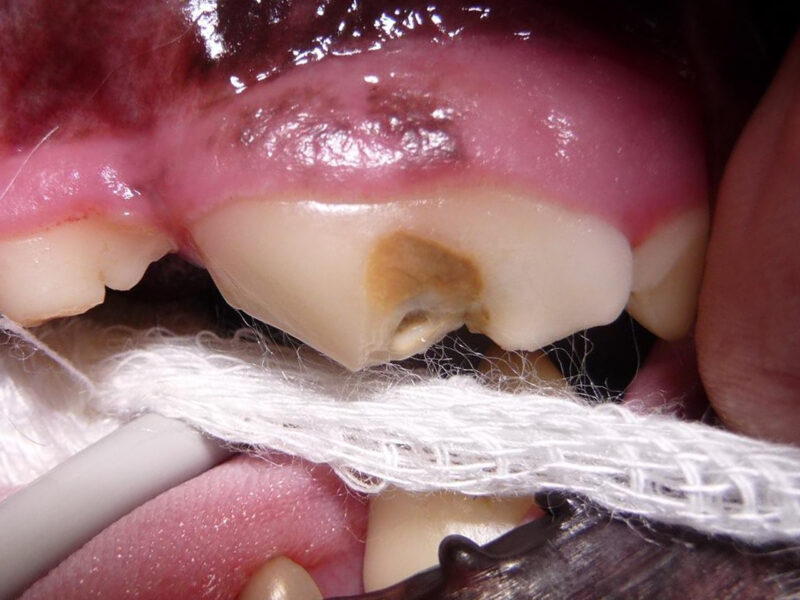

Bei Mia gibt es außer der bekannten Zahnfraktur des linken Oberkieferreißzahns (Prämolarer 4) keine Auffälligkeiten. Bei der Sondierung und Betrachtung der Bruchkante mit der Lupenbrille zeigt sich, dass noch eine ganz feine Schicht Zahnsubstanz (Dentin) Mias Wurzelkanal bedeckt. Das Dentin bietet zwar noch einen gewissen Schutz, im Gegensatz zum Zahnschmelz (der beim gesunden Zahn die äußerste Schicht der Zahnkrone bildet) hat es jedoch feine Kanälchen durch die Bakterien eindringen könnten. Im Röntgenbild zeigt sich bisher kein Hinweis für eine bestehende Infektion, und zusammen mit der Besitzerin wird entschieden, dass Mia den Zahn erstmal behalten darf, aber in sechs Monaten erneut zur Zahnröntgenkontrolle kommen muss. Da die feine Dentinschicht über dem Wurzelkanal weder vor Infektionen noch vor Umwelteinflüssen schützt, wird die Bruchkante mit dem Bohrer geglättet und der Zahn mit Kunststoff versiegelt.